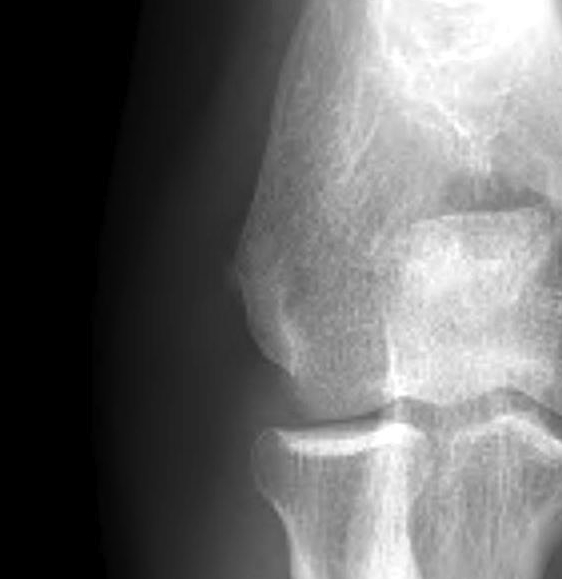

Xray

May see dystrophic calcification